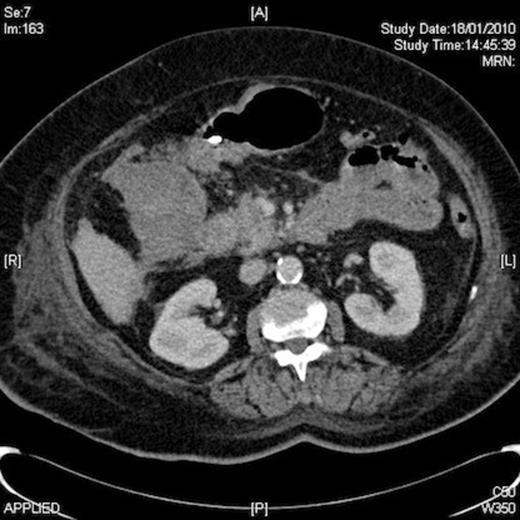

Despite no obvious cause of blood loss her haemoglobin was discovered to be low again at 8.5 gm on day 6 of admission. At this time, she received two more units of blood. An upper G I endoscopy (OGD) was arranged which revealed extensive mucosal oedema, bruising and narrowing of the first and second parts of the duodenum. CT scan of the abdomen was performed, which revealed a 10cm RUQ mass, compressing on and contiguous with 2nd part of duodenum, presumed to be a sizeable haematoma. A small amount of free blood in the peritoneal cavity and pelvis was also noted.

Once the diagnosis of gastric outlet obstruction due to compressing haematoma was established on CT, she received vitamin K and subsequently was managed conservatively under the combined care of the surgeons, haematologist, cardiologist and nutritionists. Her nasogastric tube remained in situ and it kept draining loads of biliary aspirate since her admission.

Two months following the initial episode, a follow-up OGD and abdominal CT scan were arranged. OGD showed absolutely normal stomach and duodenum. CT scan showed resolving periduodenal haematoma and resolved pelvic haemoperitoneum. She was subsequently seen as an outpatient and discharged from surgical care, with the advice to permanently stop warfarin.